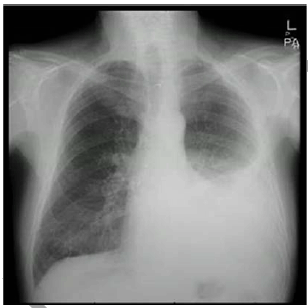

Um paciente comparece ao pronto atendimento com dispneia, tosse, dor torácica pleurítica e febre baixa, após queda na rua ocorrida há uma semana, em que houve trauma torácico. Na ocasião, foram realizados raios X de tórax.

Considerando a análise da imagem, assinale a alternativa que indica o tratamento para o alívio dos sintomas relatados no referido caso hipotético.